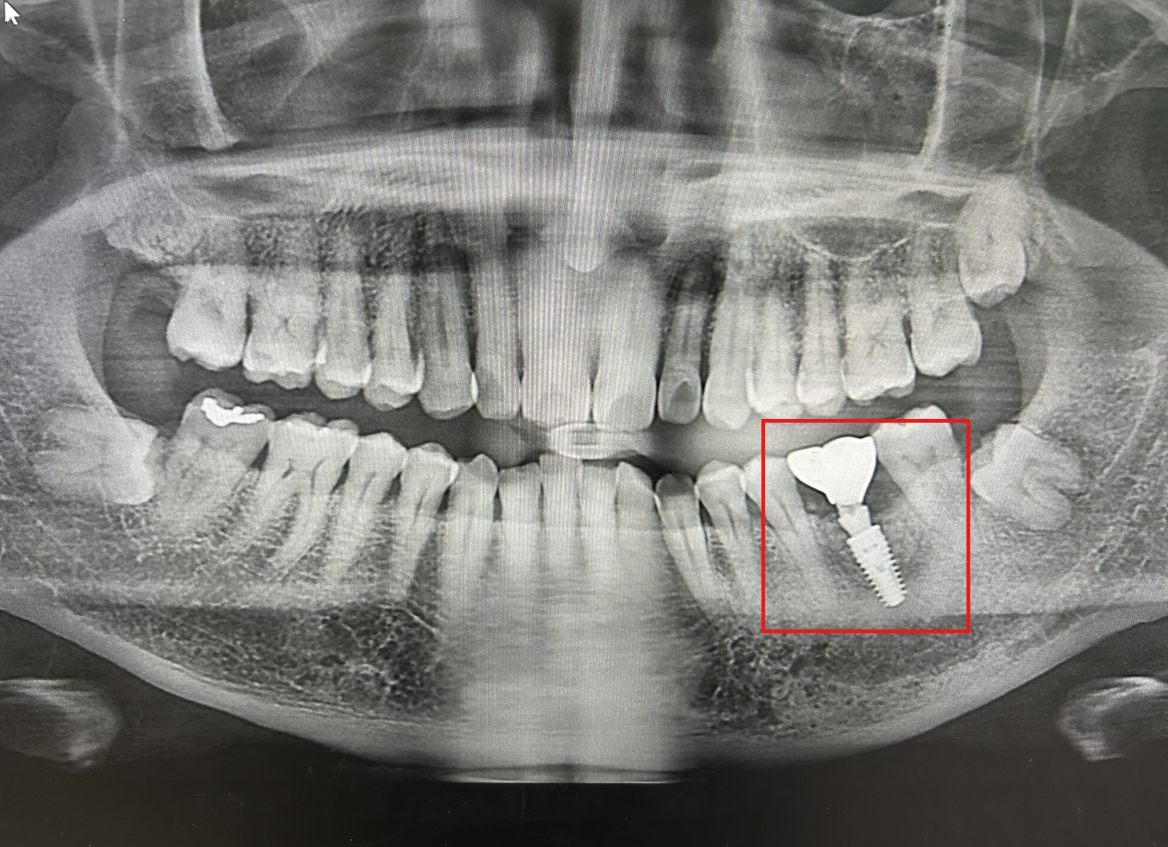

History

2023년 12월 - 치아 제거 수술

2024년 06월 - 골 유착 및 융합 (골유착률)

2024년 07월 - 나사와 치아 심기 (식립성공률)

2025년 03월 - 이상유무검사(파절저항성)

독일'의 정밀 기술!

P.S. 만 65세 이상은 2개(?) 건강보험적용 된다. 난 내 돈 거금 주고... ㅠㅠ 잇몸과 이빨관리 잘하자!